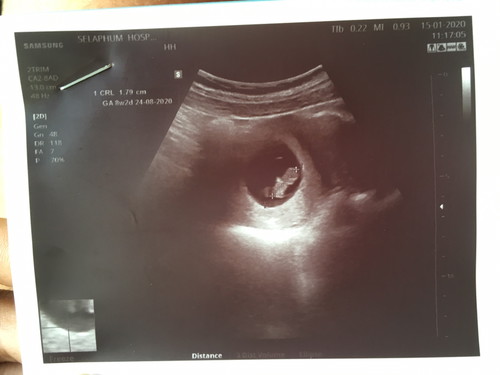

แอพคำนวน 9w2 ซาวอีกอย่าง เชื่ออันไหนดี (ตัวเล็กไปไหมค่ะ)